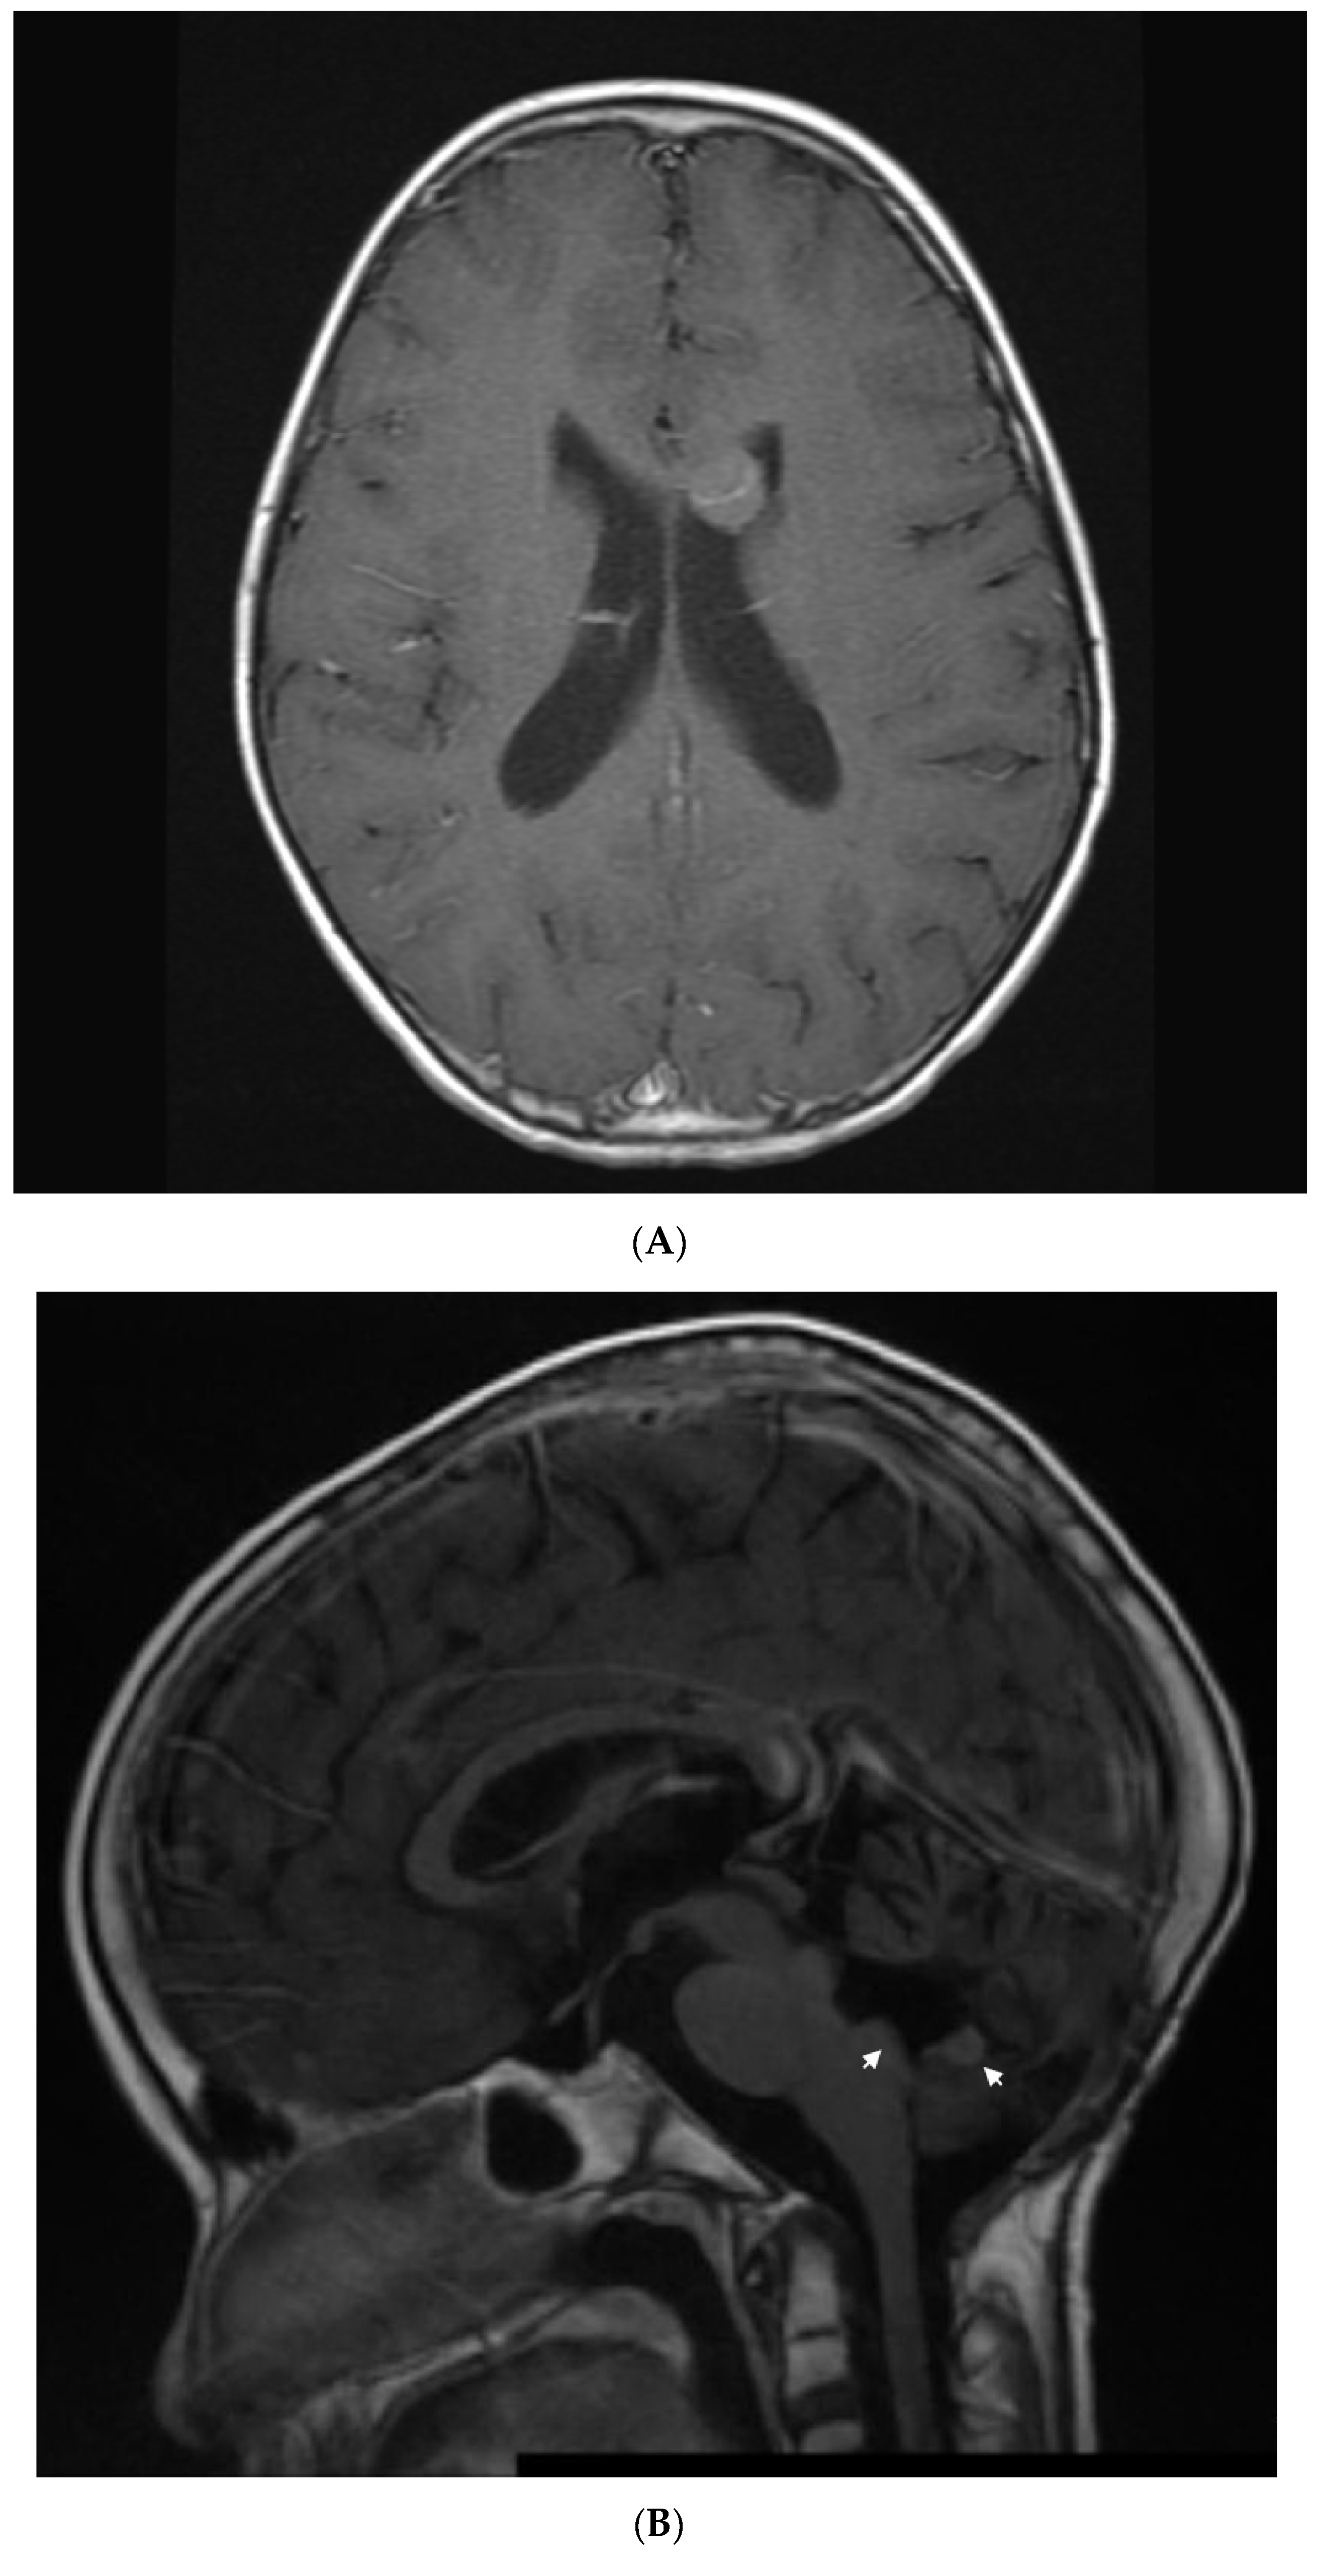

Three months off therapy, she developed a first relapse (Figure 3A) with recurrent tumors in the anterior horn of the left lateral ventricle (two), posterior horn of the left lateral ventricle (one), and anterior horn of the right lateral ventricle (one). CSF showed one abnormal cell. She was treated with 7 weeks of temozolomide followed by 1400 cGy of radiation to the ventricles and Gamma Knife surgery to a residual nodule, followed by autologous peripheral blood stem-cell transplantation (PBSCT), followed by 6 months of isotretinoin.

Figure 3.

Patient 4: (A) image shows and enhancing tumor in the anterior horn of the left ventricle when she presented with first relapse of medulloblastoma. She achieved complete remission with salvage therapy; (B) image shows an enhancing tumor involving the anterior aspect and floor of the fourth ventricle (arrows) when she presented with second relapse; (C) image shows response to 3 months of metronomic therapy with decreased size and intensity of enhancing lesions; (D) image shows interval progression of the tumor seen in T2 FLAIR resulting in a change from temozolomide to etoposide at 4 months of treatment; (E) image shows resolution of the tumor mass and T2 FLAIR changes at 8 months of metronomic therapy; (F) image shows progressive disease at 10 months of treatment.

Three months later, she experienced a second relapse (Figure 3B) with a 1.7 × 1.4 × 0.5 cm enhancing tumor in the fourth ventricle, for which she was started on metronomic chemotherapy with alternating temozolomide (60 mg/m2/day; days 1–21) and CTX (30.9 mg/m2/day; days 22–42), daily celecoxib (250 mg/m2) and VA (15 mg/kg), and bevacizumab (5 mg/kg) every 3 weeks. After 3 months on metronomic chemotherapy (Figure 3C), a partial response was documented with improved enhancing lesions in the dorsal brainstem and inferior vermis. At 4 months (Figure 3D), she developed multiple cranial nerve neuropathies and heterogeneous enhancement with mild increased volume at the left midbrain at the level of the left cerebellar peduncle, for which temozolomide was changed to VP16 (24.6 mg/m2). This was complicated by hematologic toxicity requiring several treatment interruptions and VP16 dose reductions. After 8 months on treatment, MRI showed resolution of the enhancing tumor, an interval decrease in T2 changes, and diffusion restriction in the left cerebellar peduncle (Figure 3E). After 10 months on treatment (Figure 3F), she developed an extensive infiltrative tumor involving the dorsal mesencephalon, pons, and lower brainstem, and she died of her disease 2 months later. This heavily treated patient refractory to aggressive standard salvage therapy experienced 8 months of response and survived 12 months on metronomic chemotherapy.